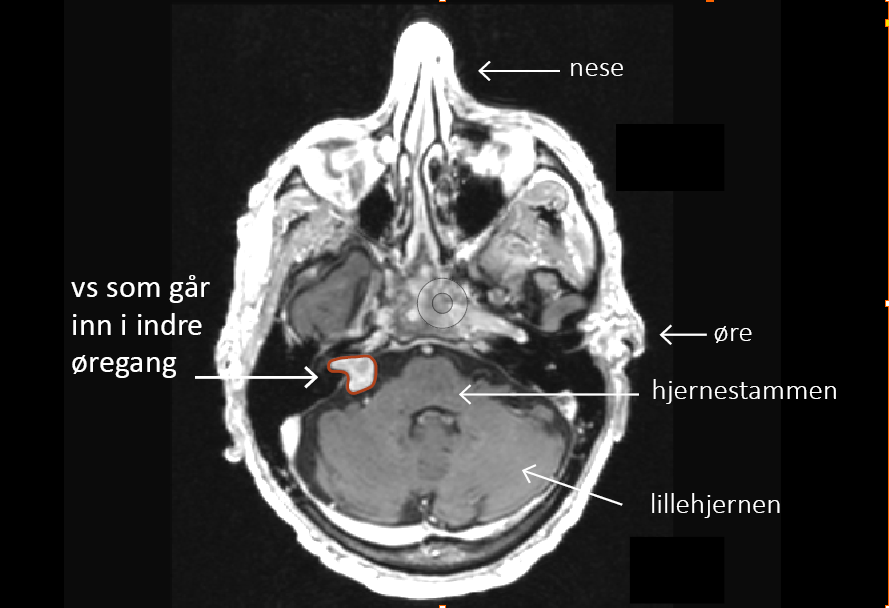

Vestibularisschwannom (VS), også kalt acusticusnevrinom eller «svulst på balansenerven», er en godartet og vanligvis langsomtvoksende svulst som vokser ut fra balansenerven i indre øregang. Derfra kan den vokse inn mot lillehjernen og hjernestammen.

MR bilde av pasient med tekstforklaring, svulst på balansenerven, indre øregang, hjernestamme, lillehjernen, øre, nese.

MR-bilde av pasient med svulst på balansenerven.